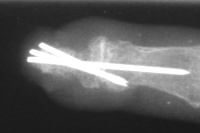

Following fingertip amputation, Hook nail deformity can result from loss of adequate supporting length of distal phalanx. This reduces the radius of curvature of the nail, and in extreme cases, the nail plate curves tightly over the end of the fingertip. One type of reconstruction involves lengthening the tip with a bone graft and skin flap, sometimes referred to as the "antenna procedure" because of the appearance of temporary pins protruding from the fingertip. One problem with this approach is that the distal bone graft may resorb slowly over the years that follow.

The small fingertip has a squared off contour and hook nail deformity following a traumatic amputation. Reconstruction was performed using a volar advancement flap and bone graft:

Xrays over this period: initial deformity, bone graft, and progressive bone graft loss over the course of years:

Image Image